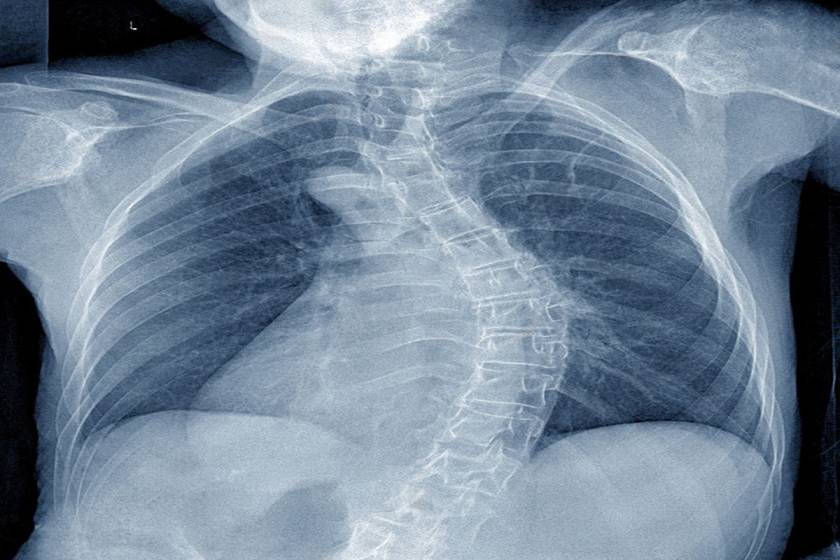

Standing full-spine X-ray showing scoliosis Cobb angle assessment in Delhi

Scoliosis describes a three‑dimensional curvature of the spine that can occur in childhood (adolescent idiopathic scoliosis—AIS), from congenital vertebral anomalies, in neuromuscular conditions, or as adult degenerative deformity. Kyphosis (excess forward bend) and combined deformities also affect posture, comfort, and pulmonary function. Most curves are mild and simply monitored; some benefit from bracing during growth; a smaller subset needs surgery to prevent progression and restore balance.

• Standing X‑rays: Full‑length AP/lateral films (or EOS if available) to measure Cobb angles, coronal balance, pelvic parameters, and sagittal alignment.